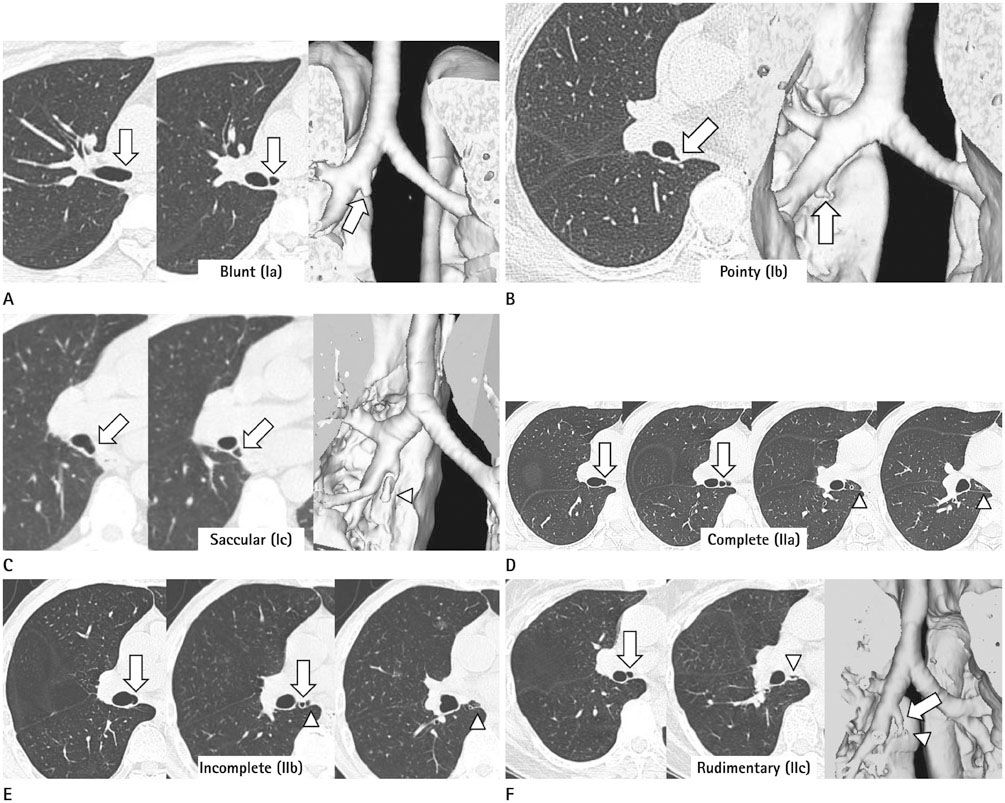

We identified two main types of ACB: blind-end (51.7%) and lobule (48.3%). The blind-end ACB was further classified into three subtypes: blunt (70%), pointy (23.3%) and saccular (6.7%). The lobule ACB was also further classified into three subtypes: complete (46.4%), incomplete (28.6%) and rudimentary (25%). Division location to the upper half bronchus intermedius (79.3%) and medial direction (60.3%) were the most common in all patients. The difference in division direction was statistically significant between the blind-end and lobule types (p = 0.019). Peribronchial soft tissue was found in five cases. One calcification case was identified in the lobule type. During follow-up, ACB had disappeared in two cases of the blind-end type and in one case of the rudimentary subtype.

The proposed classification of ACB based on imaging, and the follow-up CT, helped us to understand the various imaging features of ACB.